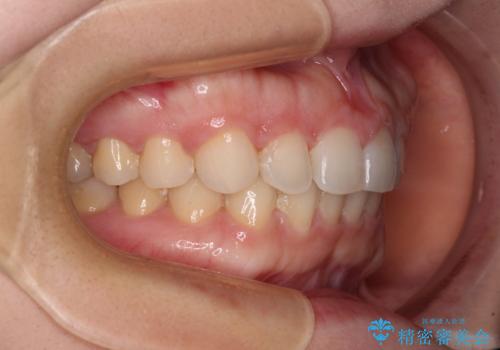

ギリギリとなりましたが、結婚式直前にワイヤー装置を外すことができました。

ワイヤー装置除去後に細かい部分を短期間のマウスピース矯正にて仕上げました。